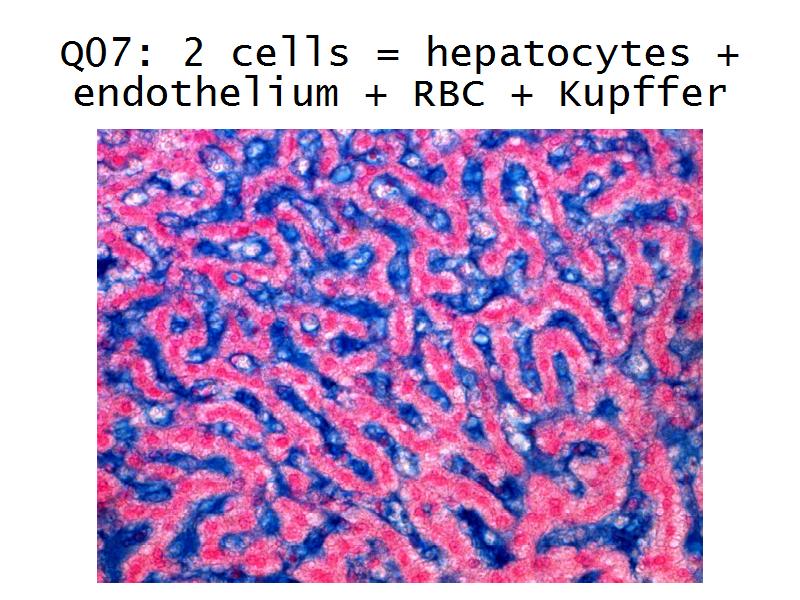

- Liver =

- Liver = squamous, cuboidal